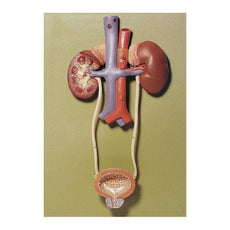

Dual Gender Urinary System, 6-part

Dual Gender Urinary System, 6-part - Includes 3B Smart Anatomy

This Urinary System all-in-one-model shows:- Structures of retroperitoneal cavity

- Large and small pelvis with bones and muscles

- Inferior vena cava

- Aorta with its branches including iliacal vessels

- Upper urinary tract

- Rectum

- Kidney with adrenal gland.

One front half of a kidney is removable from the anatomical model of the urinary system. With easy to change male insert (bladder and prostate, front and rear half) and female insert (bladder, womb and ovaries, 2 lateral halves) the Urinary System model is a great teaching tool.

Dual Sex Urinary System model on baseboard.